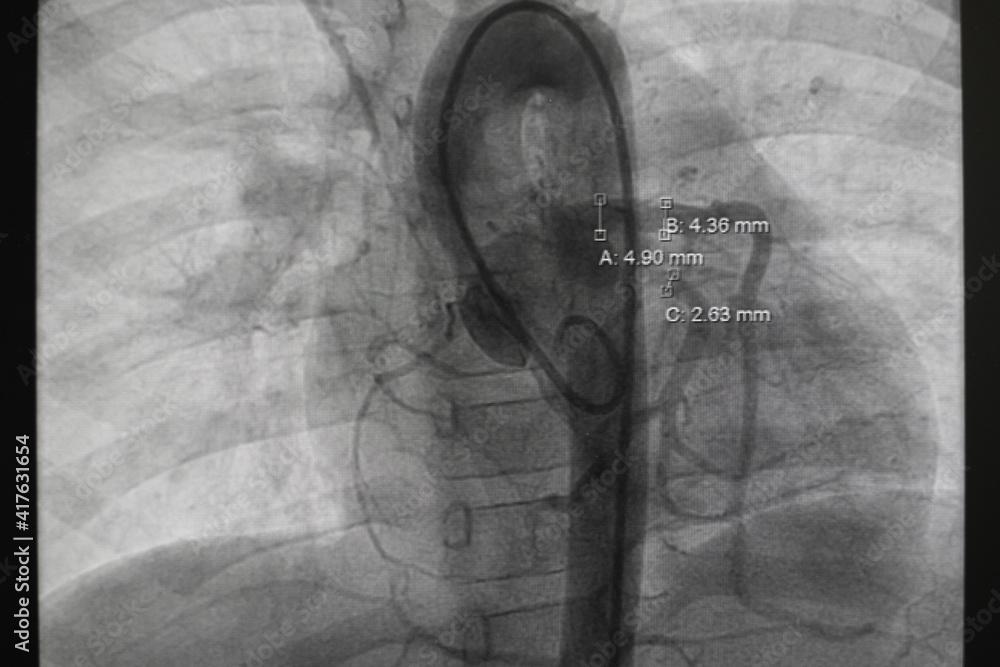

From stock.adobe.com

pediatric angiography. Aortography showed patent ductus arteriosus (PDA Pda Heart Catheterization The procedure involves making a small incision, typically in the groin, and inserting a small. Patent ductus arteriosus (pda) is a heart defect found in the days or weeks after birth. A pda is a heart defect that occurs when a blood vessel called the ductus arteriosus fails to close after birth, as it normally should. Specialized heart doctors called. Pda Heart Catheterization.